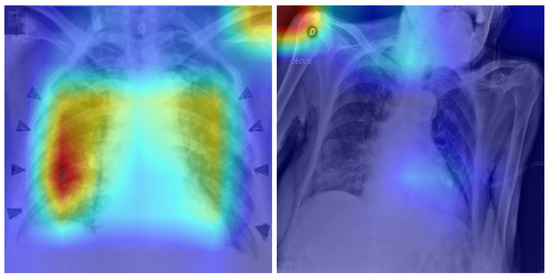

Pandemics emphasize the importance of real-time, interpretable clinical decision-support systems for identifying high-risk patients and assisting with prompt triage, particularly in data-intensive healthcare systems. This paper describes a novel dual big-data pipeline that includes (i) a streaming module for real-time epidemiological hospitalization risk prediction and (ii) a supplementary imaging-based detection and reasoning module for chest X-rays, with COVID-19 as an example. The first pipeline uses state-of-the-art machine learning algorithms to estimate patient-level hospitalization risk based on data from the Centers for Disease Control and Prevention’s (CDC) COVID-19 Case Surveillance dataset. A Bloom filter accelerated triage by constant-time pre-screening of high-risk profiles. Specifically, after significant experimentation and optimization, one of the models, XGBoost, was selected because it achieved the best minority-class F1-score (0.76) and recall (0.80), outperforming baseline models. Synthetic data generation was employed to mimic streaming workloads, including a strategy that used the Conditional Tabular Generative Adversarial Network (CTGAN) to produce the best balanced and realistic distributions. The second pipeline focuses on diagnostic imaging and combines an advanced convolutional neural network, EfficientNet-B0, with Grad-CAM visual explanations, achieving 99.5% internal and 99.3% external accuracy. A lightweight Generative Pre-trained Transformer (GPT)-based reasoning layer converts model predictions into auditable triage comments (ALERT/FLAG/LOG), yielding traceable and interpretable decision logs. This scalable, explainable, and near-real-time framework provides a foundation for future multimodal and genomic advancements in public health readiness. Full article